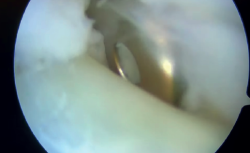

El paciente presentó un postoperatorio correcto en el cual se realizó un protocolo de inmovilización postoperatoria con movilización temprana y fisioterapia enfocada en mejorar la movilidad y fortalecer la musculatura del tobillo, con mejora en cuanto al dolor y la inestabilidad subjetiva. Un año después, el paciente volvió a consultar por dolor localizado en la cara posterolateral del tobillo. A la exploración, presentaba hinchazón lateral e hiperalgesia sobre el maléolo lateral. El rango de movimiento estaba preservado. Además, se evidenció dolor durante los movimientos de eversión. El paciente describió una sensación de chasquido en la cara lateral del tobillo. La prueba de cajón anterior no era negativa, por lo que cabía considerar la posibilidad de un fracaso de la reparación o aflojamiento de las plastias ligamentosas. Las radiografías simples demostraron que no había desplazamiento del dispositivo de fijación de la fíbula, como se muestra en la Figura 1.

Figura 1. Control radiográfico postoperatorio donde se ve el anclaje TightRope® en la parte posterior del peroné.